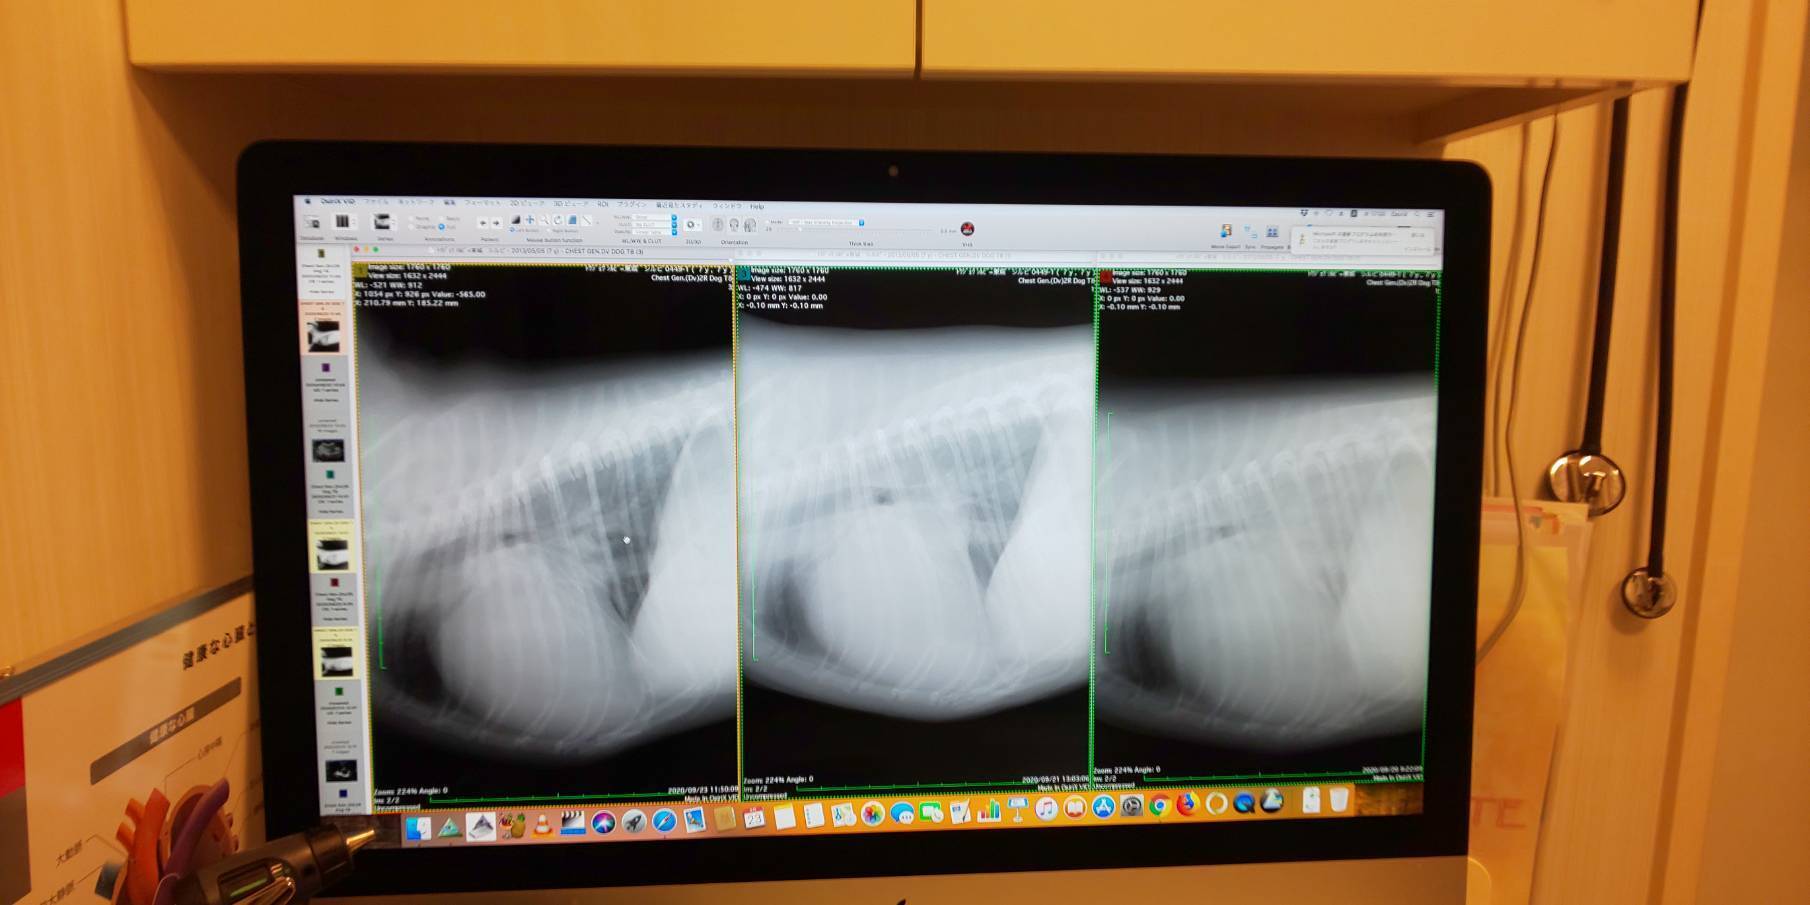

横からのレントゲン右から入院当日、1日後、3日後。

右上の三角形の所が肺で白くなってるのが水が溜まっているからです。徐々に白い影が無くなってるのが分かります。三角形の、左下の白いのは心臓でかなり大きくなってます。